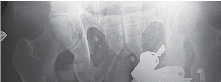

2. التصوير بالأشعة السينية (X-ray):

تُعد الأشعة السينية هي الأداة التشخيصية الأساسية لتقييم خشونة الركبة. يلتقط الأستاذ الدكتور هطيف صورًا للركبة من زوايا مختلفة، بما في ذلك صور الوقوف (Weight-bearing X-rays)، والتي تُظهر المفصل تحت تأثير وزن الجسم الطبيعي. تُظهر الأشعة السينية ما يلي:

- تضييق المسافة المفصلية: خاصة في الجانب الإنسي للركبة، مما يشير إلى تآكل الغضروف.

- تكون النتوءات العظمية (Osteophytes): وهي نتوءات عظمية صغيرة تتشكل حول حواف المفصل نتيجة للتآكل.

- تغيرات في كثافة العظام: مثل التصلب تحت الغضروفي (Subchondral Sclerosis).

- درجة الانحراف التقوسي: قياس الزوايا المحورية للساق لتحديد مدى التقوس بدقة.